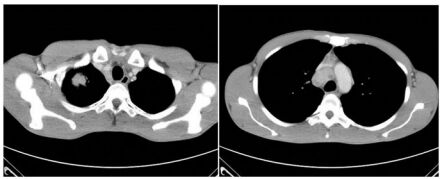

45. 65 歲女性病人,健檢意外發現右上肺有一顆腫瘤,縱膈腔也有數顆淋巴結(N2 multiple station Gr 2,4,7),如下圖,正子掃描無遠端轉移,無對側及鎖骨上淋巴結。腫瘤切 片為肺腺癌,無驅動基因突變,PD-L1(22C3)免疫染色 5%,下列治療方式何者較為適當? (A) 手術切除再接受術後輔助化療。 (B) 前導性化療(Neoadjuvant chemotherapy)後再接受手術切除。 (C) 不適合開刀,化療合併免疫治療是首選。 (D) 同步化放療(concurrent chemoradiotherapy)疾病無惡化再接受一年免疫治療作為鞏固 治療。